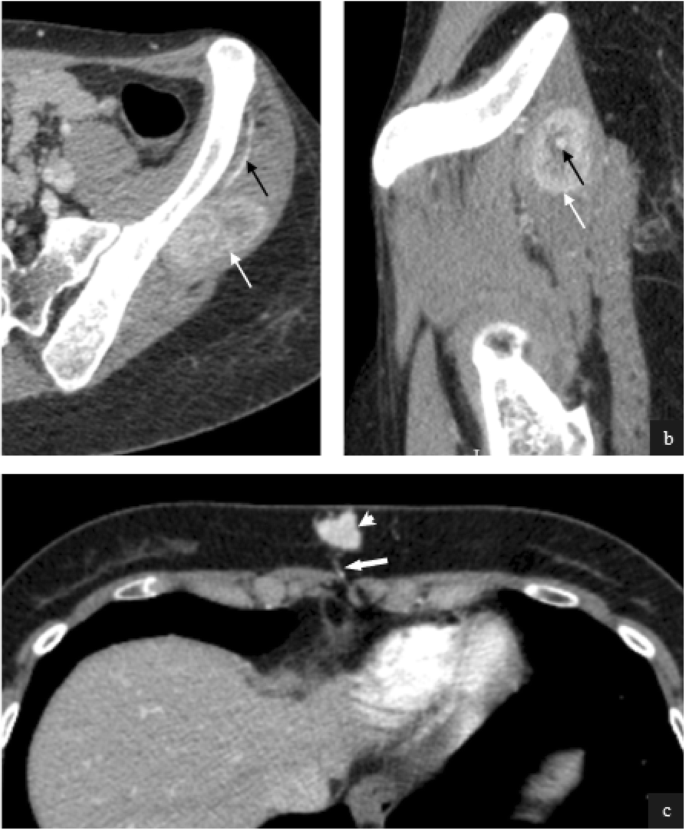

Lymph node metastases were identified in 7/32 patients (22%), with 5 mediastinal metastases and 1 mediastinal with pelvic side-wall. All nodes demonstrated necrosis and hypervascularity, (Fig. 7) with prominent feeding vessels identified in 4/7 (57%).

Contrast enhanced axial CT in three patients with nodal metastases from primary ASPS (a-c). Left hilar nodal tissue in a 31 year old male patient demonstrates high attenuation with prominent central vessels (a, white arrow). Feeding vessels are demonstrated alongside and within nodal disease in a 37 year old male patient (b, black arrow). Metastatic mediastinal nodal disease in a 28 year old female (c) demonstrates marked central necrosis, however peripheral hypervascularity is still appreciated (c, black arrowheads)

Intramuscular (4/ 32, 13%) and subcutaneous metastases (1/32, 3%) were also featured. Metastases in these locations were characterised by hypervascularity with demonstrable feeding vessels (Fig. 8). The pattern of distant bone metastases (5/32, 13%) in our cohort was varied with lytic, mixed lytic and sclerotic and sclerotic-only metastasis appreciated (Fig. 9). Soft tissue components were observed in 3/5 cases (60%).

Intramuscular and subcutaneous metastases from ASPS. Post contrast axial (a) and sagittal CT (b) in a 21 year old female with an intramuscular metastasis (a & b, white arrows) demonstrates a large feeding vessel (a & b, black arrows). Post contrast axial CT in this 28 year old female patient demonstrates markedly hyperenhancing subcutaneous metastasis (c white arrowhead) inferior to the xiphisternum. Again a small feeding vessel is appreciated (c, thick white arrow)